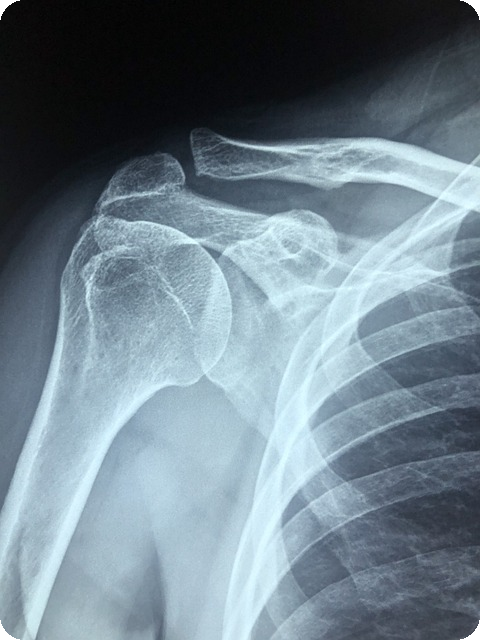

| X-ray 촬영 | 어깨 힘줄 내에 칼슘 침착을 확인 | 간편하고 빠름 |

X-ray는 가장 흔히 사용되는 방법으로, 하얗게 보이는 칼슘 침착을 확인할 수 있습니다. 하지만 칼슘이 작거나 깊숙한 경우 X-ray로 확인하기 어려울 수 있습니다. 이럴 때는 초음파 검사를 통해 실시간으로 자세한 상태를 알 수 있습니다. 필요에 따라 MRI 검사를 통해서 더욱 세부적인 진단을 받을 수 있습니다.